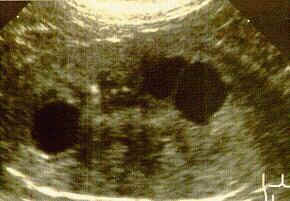

Niere einer 6 Wochen alten Katze mit PKD